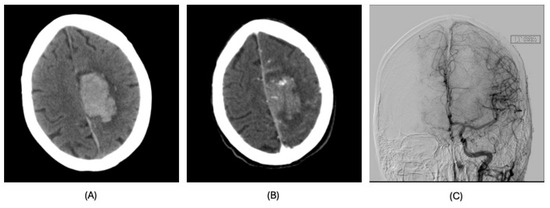

| Diagnosis | Lobar intracranial hemorrhage (ICH) | Basal Ganglia ICH | Lobar ICH | Embolic ischemic stroke (IS) | Embolic IS | |

| Clinical Syndrome | Left headache, right hemianopia | Persistent drowsiness post-OLT, GCS E1VTM2, dilated right pupil | Headache, right hemiparesis, right lower limb sensory deficits | Aphasia | Altered mental status, right gaze preference, left flaccid paralysis | |

| Imaging | CT scan | CT scan | CT scan MRI CT angiography | CT scan MRI MR angiography | CT scan CT angiography MRI | |

| Findings | CT: Left occipital intraparenchymal hematoma Volume: 15 mL | CT: Large right frontal temporal parenchymal hematoma, severe surrounding mass effect with leftward midline shift, right uncal herniation Volume: 93.5 mL | CT: Right frontoparietal parenchymal hematoma with locoregional mass effect, rightward midline shift Volume: 25 mL | CT: Left occipital infarct Transcranial doppler: 2 spontaneous emboli, more than 100 high intensity transient signals (HITS) in bilateral middle cerebral arteries (MCAs) after agitated saline | CT: Right parietal lobe hypodensity Transcranial doppler: more than 300 HITS in bilateral MCAs after agitated saline | |

| Management | Conservative | Non-operative in view of poor prognosis | Endoscopic left craniotomy for evacuation of hematoma | Conservative | Conservative management; tracheostomized and decannulated 1 month after CVA | |